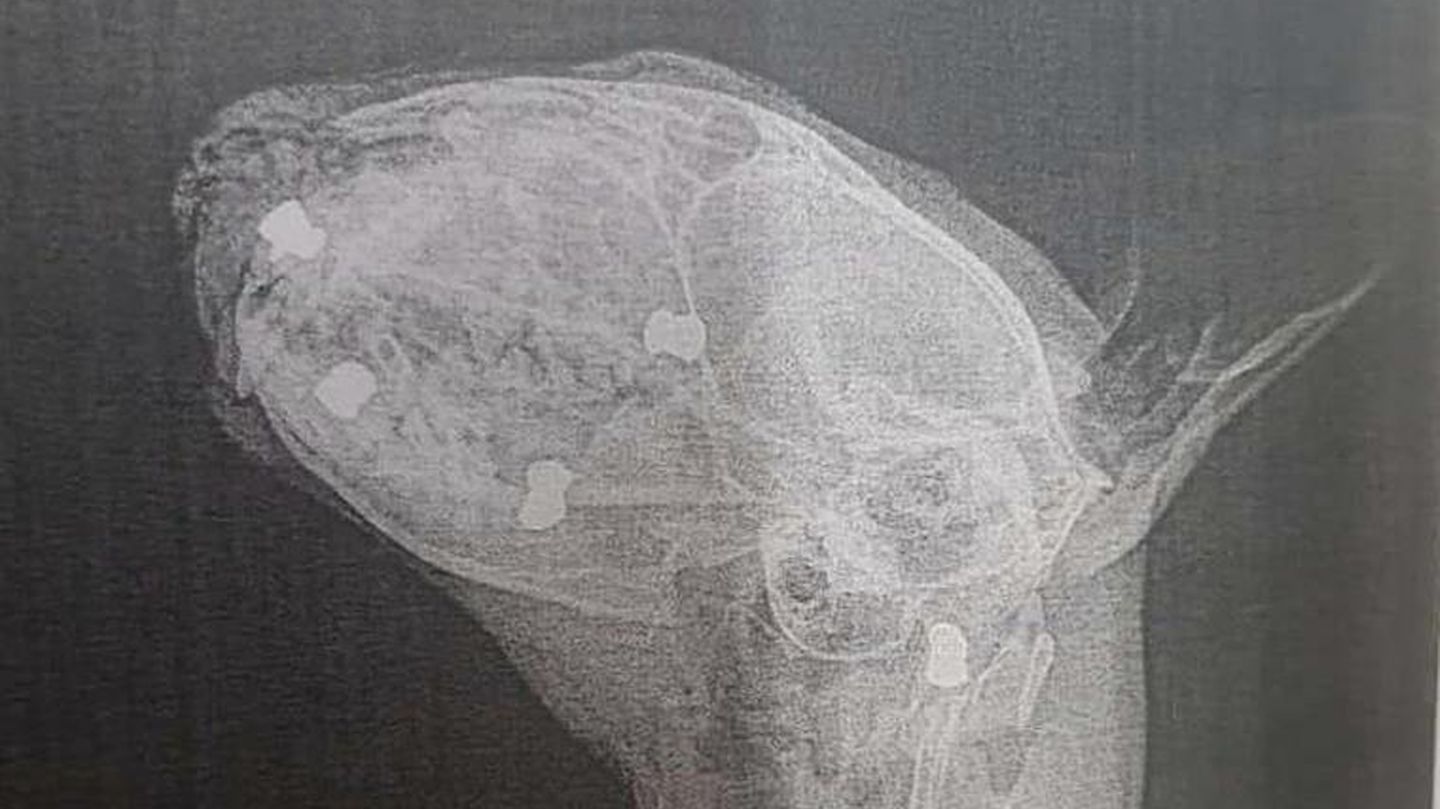

Wie zunächst die "Mainpost“ berichtet hatte, wurde Kater Paulchen Ende August schwerverletzt zum Tierarzt gebracht. Doch der Mediziner konnte nichts mehr für das Tier tun. Später konnten auf den Röntgenbildern der Ursprung, sowie das ganze Ausmaß von Paulchens Leiden festgestellt werden. Insgesamt 24 Projektile, mutmaßlich aus einer Luftdruckwaffe, steckten im Körper des Vierbeiners. "Ein Schuss ging in die Lunge, der Rest in den Kopf und entlang der Wirbelsäule", wie die "Mainpost" berichtete.